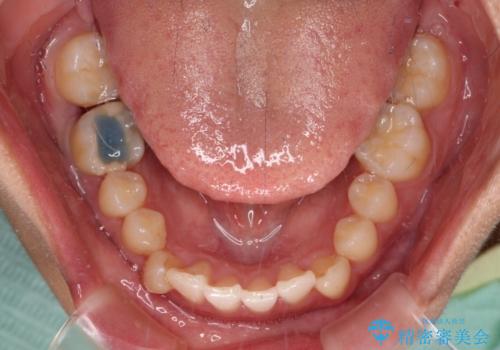

矯正治療途中で右下奥歯の虫歯治療を近医で行ったようで、既に神経が失活していたと合わせて矯正治療後に補綴治療を行う予定です。